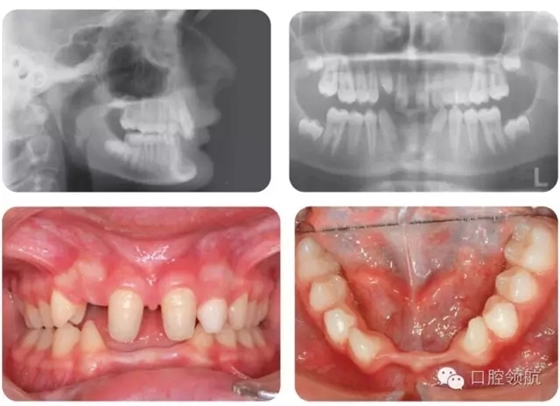

嚴重STHAG相關的主要臨床特征有哪些?(圖2.18)

圖2.18

● 嚴重的STHAG常與后縮側(cè)貌相關,伴下前面高減小。垂直比例減小的病例常導致覆加深。

● 口內(nèi)特征根據(jù)只有1顆牙先天缺失的輕度病例或超過6顆牙缺失的重度病例而不同。嚴重病例通常有散在間隙和乳牙滯留。

● 常伴隨過小牙,可以是局部(釘狀側(cè)切牙)或廣泛的。

● 很多病例的滯留乳牙可以保留至成人階段。下沉的乳磨牙往往提示繼承恒牙缺失。

● 多顆牙缺失的病例,繼承恒牙缺失可導致頜骨發(fā)育不全,牙槽嵴狹窄。有時會出現(xiàn)側(cè)方開牙合。